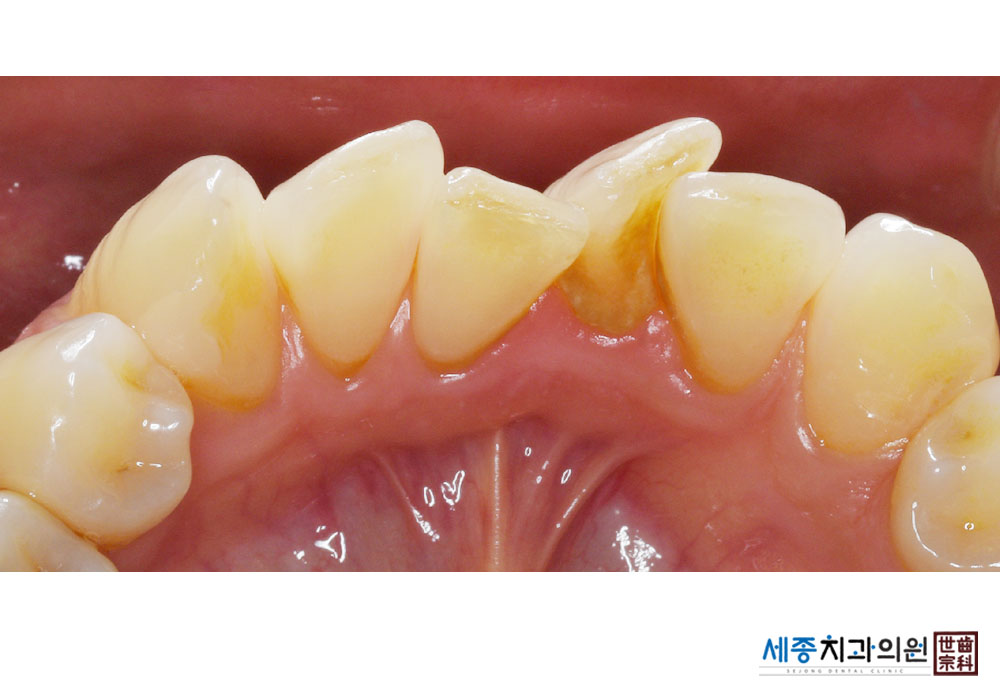

[스케일링] 치주질환 예방 스케일링

치료전 : 2023-10-11

치료후 : 2023-10-11

가글마취&저주파 스켈러를 사용한 착색제거 스케일링